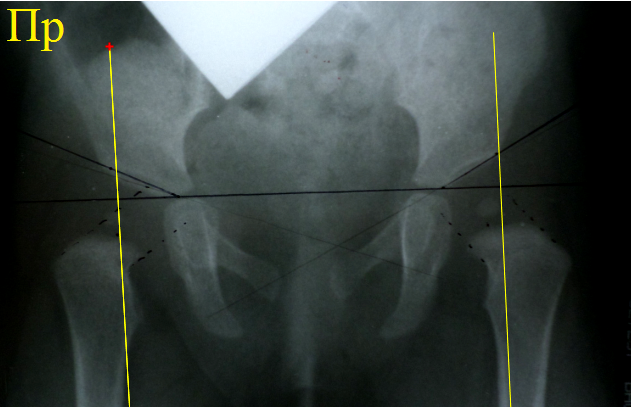

Снимок

того же ребенка, что в предыдущем примере. Выполнено расчерчивание по схеме

Садофьевой. Справа ось головки пересекает линию крыши во второй четверти, что

относится к норме. Слева ось головки

пересекла линию крыши в третьей четверти, что свидетельствует о дисплазии

сустава. Рисунок отчетливо демонстрирует недостаток схемы, связанный с

трудностью правильного проведения оси шейки бедра. Схема крайне чувствительна к правильности

укладки.

Расчерчивание очень простое. Проводится касательная горизонтальная линия к

верхним краям теней обеих бедренных костей. Затем строго перпендикулярно ей

проводятся две касательные вертикальные линии к внутренним краям теней обеих

бедренных костей. Эти линии являются указательными стрелками. Если вертикальная

линия пересекает крышу вертлужной впадины по центру или во внутренней её

половине, то головка бедра на искомой стороне центрирована. Если же линия

пересекла крышу вертлужной впадины в её наружной половине или вообще за

границами впадины, то имеется децентрация сустава. Расстояние от горизонтальной линии до точки

пересечения вертикальной линией крыши вертлужной впадины должно быть одинаковым

справа и слева.

Предыдущий

снимок расчерчен по схеме Путти. Слева перпендикуляр пересекает крышу

вертлужной впадины в наружной части, справа – практически по центру. Расстояние от горизонтальной линии до крыши

впадины слева больше. Децентрация тазобедренного сустава слева не вызывает сомнений, центрированное положение правого сустава не

очень наглядно, при желании его тоже можно признать децентрированным. Схема

вполне годная для работы, также чувствительна к правильности укладки.